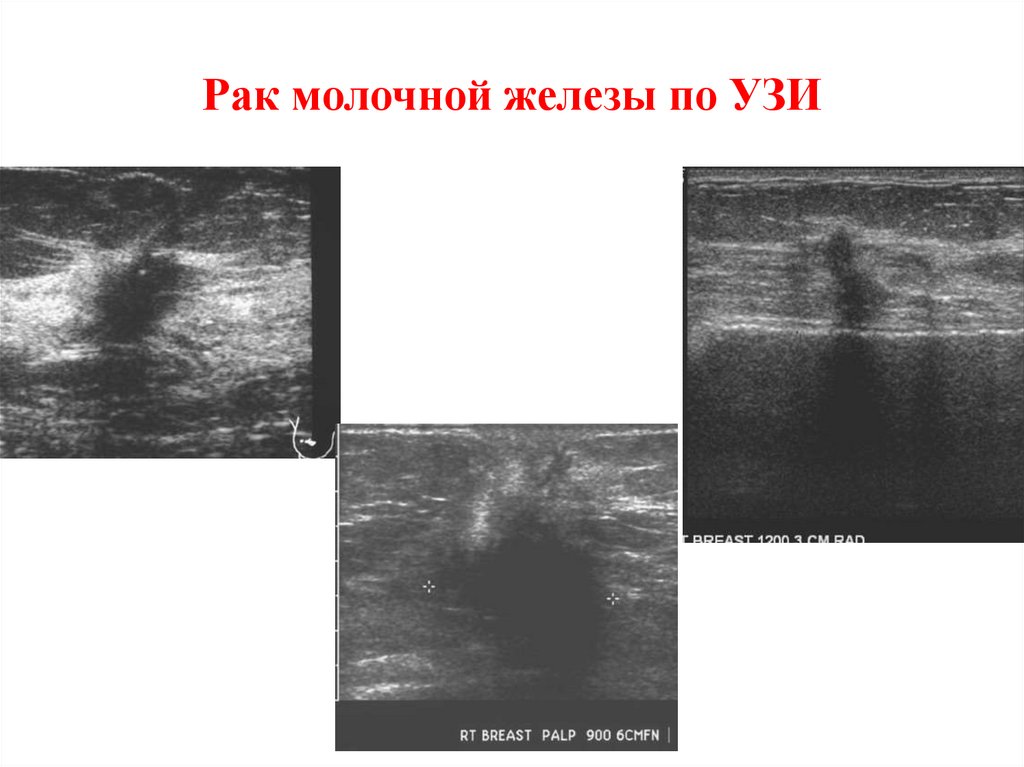

Рак молочной железы по УЗИ

27. Рак молочной железы по УЗИ